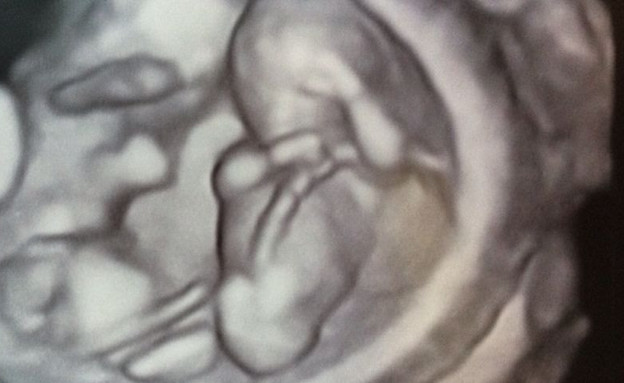

הגשתי לו את תמונת האולטראסאונד שקיבלתי לפני שעתיים, עדיין בשוק מעצמי שהצלחתי להתאפק שלא להתקשר אליו כל הזמן הזה ולצרוח באושר את הבשורות המדהימות הללו. הוא אמנם לא טכנאי רנטגן, אבל לא היה קשה להבין על מה הוא מסתכל. בתוך הרקע השחור הזה שהוא הרחם שלי נצצו להן שתי נקודות לבנות שסיפרו לנו שהחיים שלנו הולכים להשתנות. יש לי בבטן תאומים.

אחרי הגילוי המרגש נשארו לסוף סקירת המערכות רק עוד שעתיים של בהייה במסך והעמדת פנים שאנחנו מבינים מה אנחנו רואים (כן, כן, הלבלב, ישר זיהיתי) לא כולל שלוש הפסקות פיפי באמצע ועוד הפסקת חטיף שוקולד כדי שאחת העצלניות תסתובב. בדיקות רפואיות בהריון תאומים זה דבר ארוך ומתיש (ויקר. מאד). מכיוון שלא הסתפקתי רק בסקירות דרך הקופה והלכתי לסקירות מערכות גם באופן פרטי, כולל בדיקת שקיפות עורפית ודיקור מי שפיר (כפול!!!!) זו לא תהיה הגזמה לומר שביליתי את רוב השליש השני של ההיריון בניגוב שאריות ג'ל אולטראסאונד דביק מהבטן. לפחות אצל הרופא הפרטי הג'ל היה חם ולא קפוא כמו בקופת חולים. הי, השארתי פה 3000 שקל, זה המעט שאוכל לקבל.